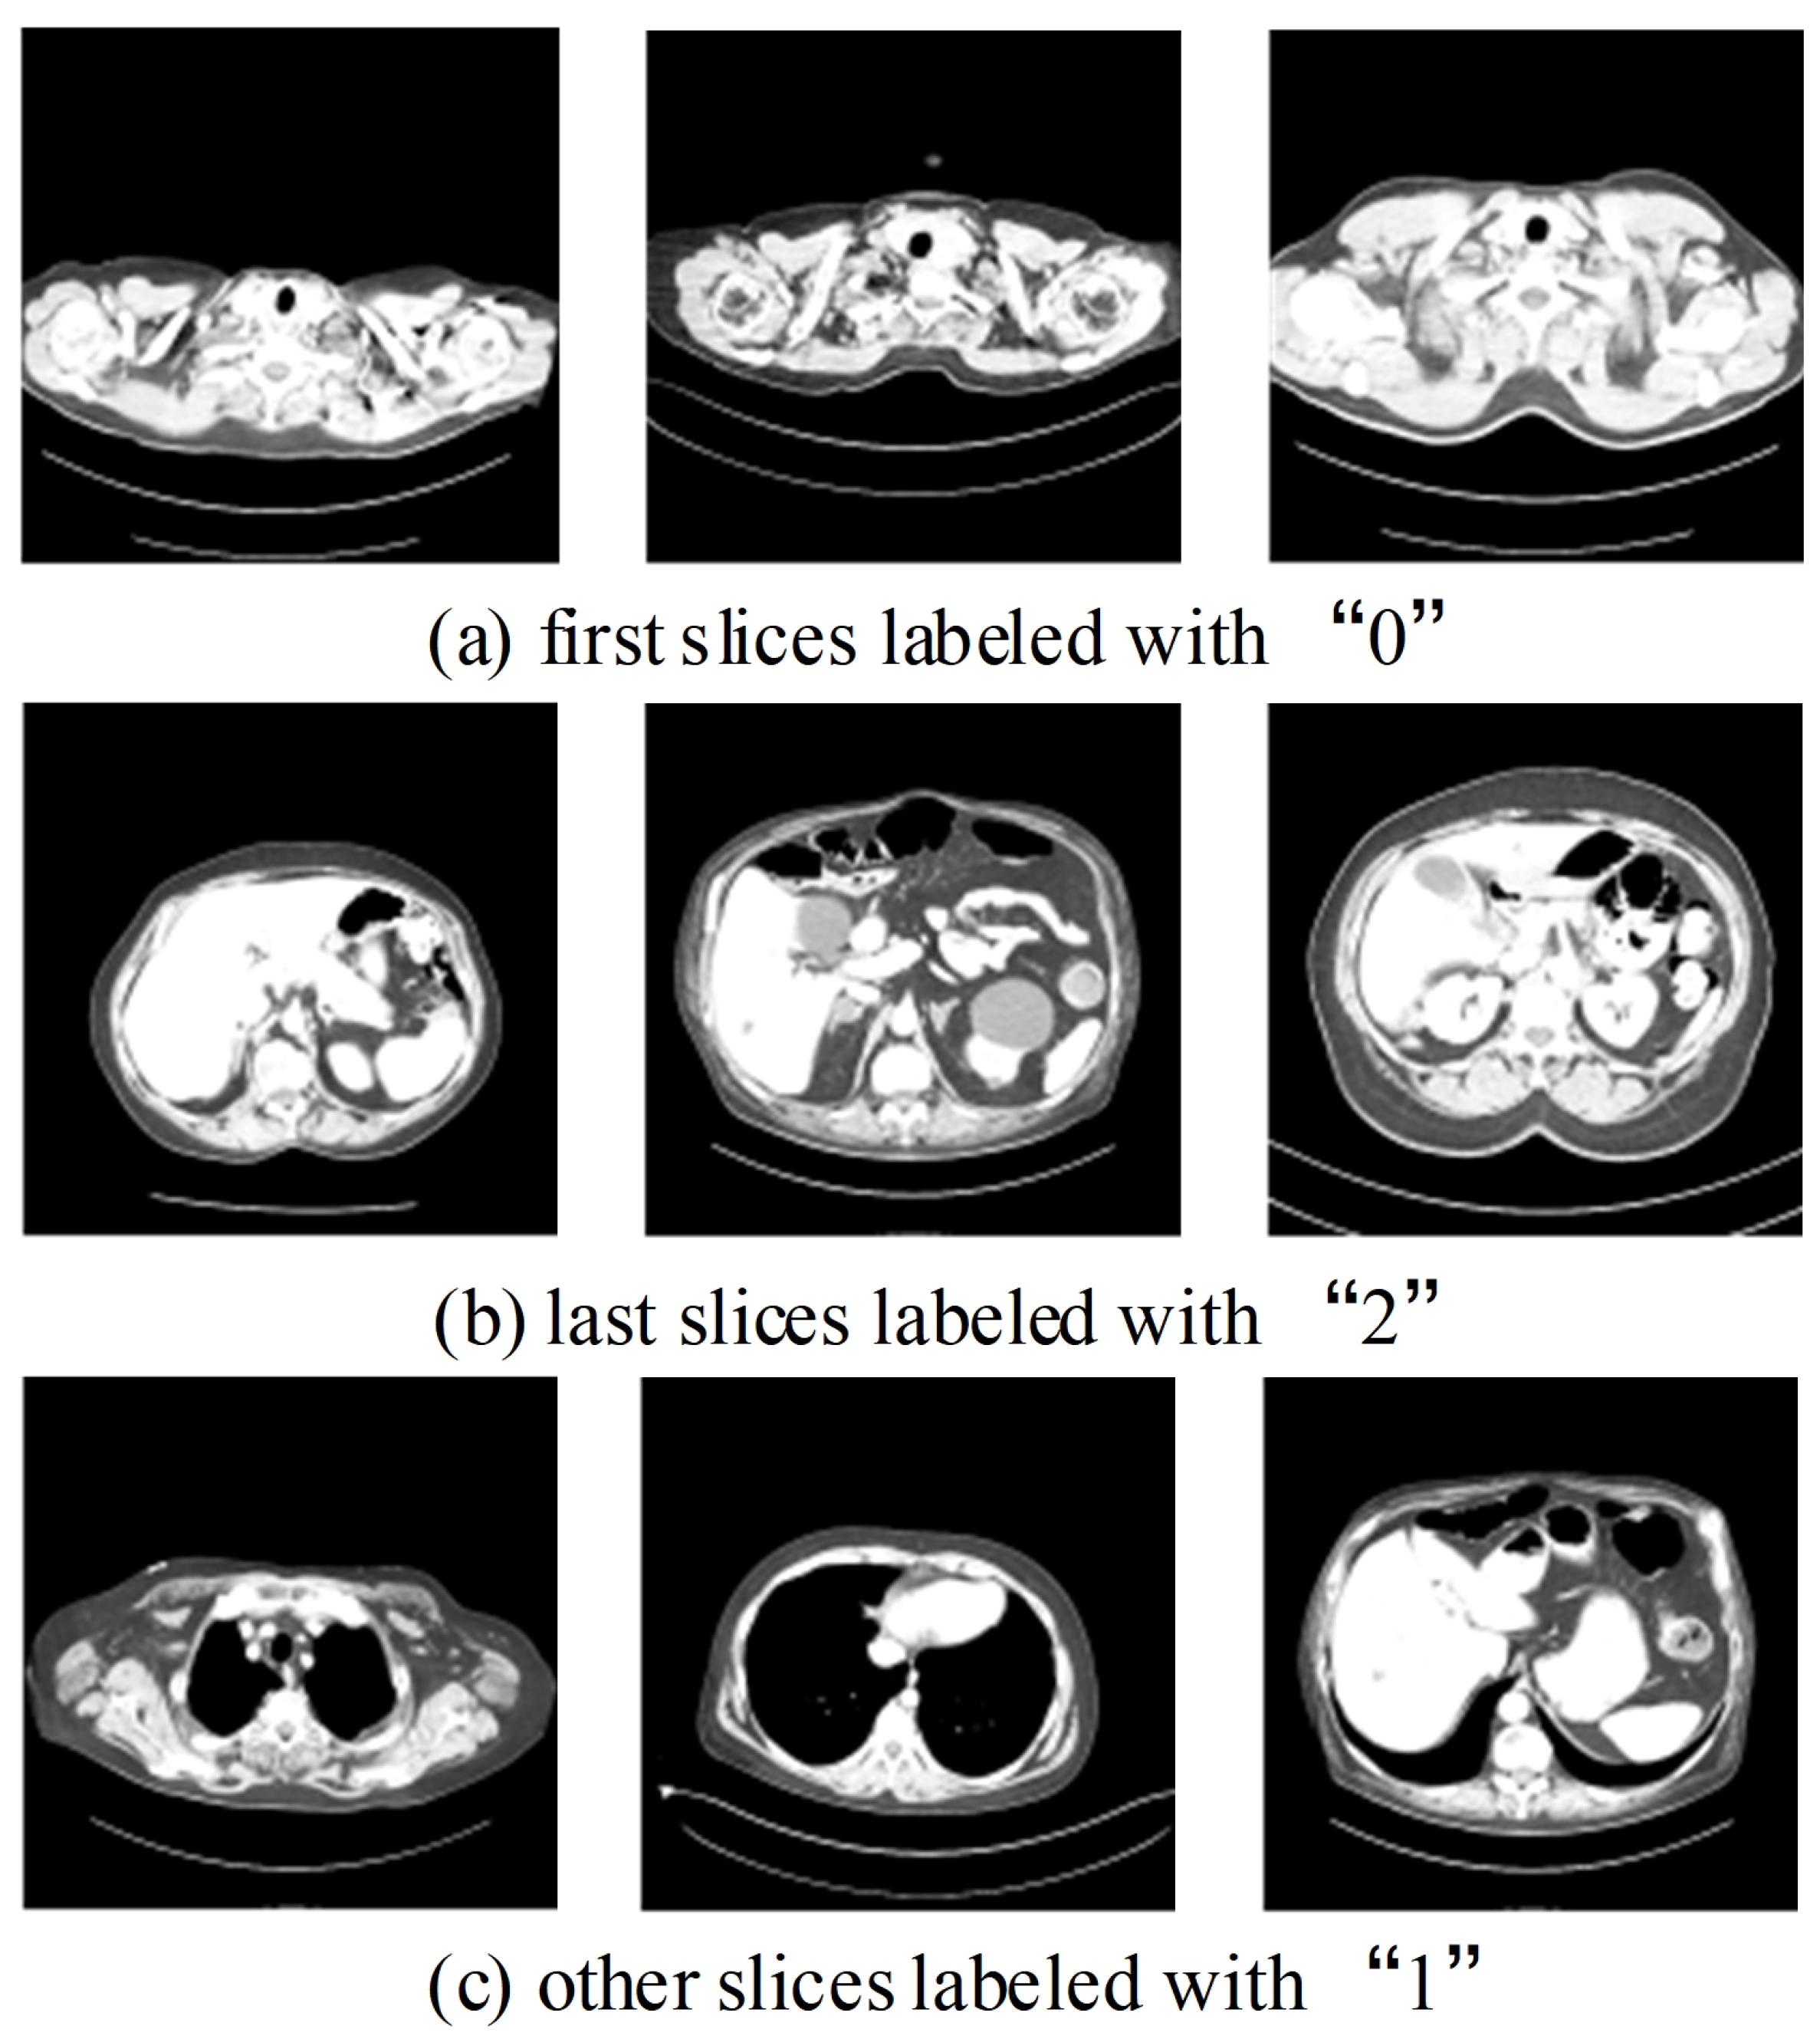

We conducted a multi-class classification to localize the lung slices and labeled them based on their position in the CT image as ‘0’, ‘1’, or ‘2’ (Figure 6). ‘0’ signifies the first slice of the lung, ‘2’ denotes the last slice of the lung, and any other slices outside of these boundaries are labeled as ‘1’ (as depicted in Figure 6).

Figure 6. Examples of three classes of localization labels. There are large differences in the size of body tissues between different cases, which brings difficulties to the training and testing effects of the model.